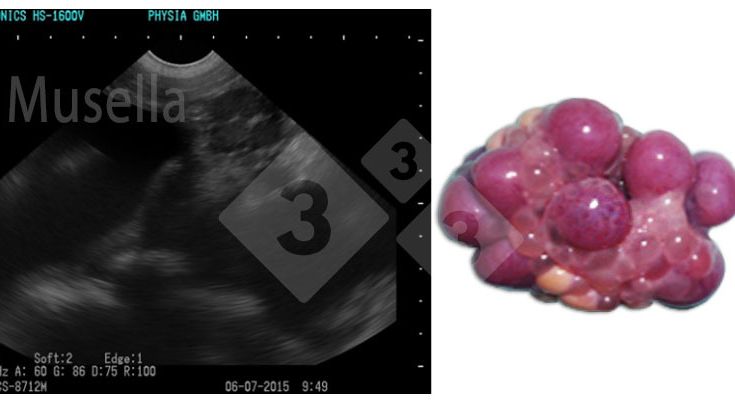

Ultrassom de precisão em fêmeas suínas: muito mais do que controle da gestação!

O ultrassom pode ser usado para visualizar as estruturas ovarianas, avaliar o estado puberal e diagnosticar patologias ovarianas.